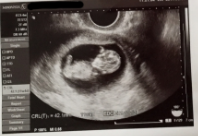

みんなの妊娠10週目のエコー写真をご紹介します。

10週0日(10w0d・女の子)|しぃ~ちゃん さん(21歳)

このエコー写真が1番好きです!

まだちゃんと手の形にもなってなくてクリオネちゃんみたいな感じがたまらなく可愛いです!